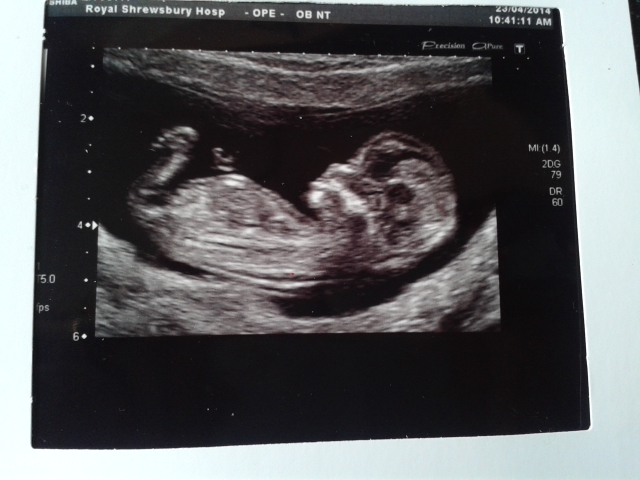

Hello. Just wondering if anyone could kindly look at my scan pics and tell me whether they think boy or girl? I'm confused because they both look girly to me and I have put lines on the one. Thanks in advance. Xx

I lean blue

I do as well slightly to be honest it's just confusing as the one nub looks girly. Thanks for guessing :-)

It doesn't look all that girly to me. I am sure you will get more guesses in a bit.

I think it looks boyish because of the stacking on top of the nub but I c